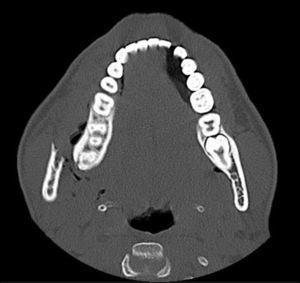

Se solicitó radiografía simple (Figura 1) que mostró fractura completa de rama mandibular derecha y fractura lineal parasinfisaria izquierda. Ante la no disponibilidad de ortopantomografía de urgencia se solicitó tomografía computarizada mandibular que evidenció fractura desplazada del ángulo mandibular derecho, con enfisema subcutáneo (Figura 2) y fractura parasinfisaria izquierda no desplazada.

Figura 2. Fractura desplazada del ángulo mandibular derecho, con enfisema subcutáneo en jugador de hockey hierba de 17 años con contusión facial directa.

Para el diagnóstico de las fracturas mandibulares, la radiografía panorámica u ortopantomografía proporciona una primera visión general muy aceptable, pero en muchos servicios de urgencias dicha prueba no está disponible. En estas situaciones, la radiología simple con proyección AP (Figura 1), Townes y oblicua lateral derecha e izquierda, generalmente permite visualizar la fractura, pero en caso de radiografía aparentemente normal y alta sospecha diagnóstica, se debería solicitar una tomografía computarizada mandibular (Figura 2). La tomografía computarizada es el estudio óptimo para la visualización de la mandíbula en todos los planos y, sobre todo, de los cóndilos. Estos frecuentemente están desplazados por la tracción de la musculatura masticatoria y se encuentran fuera de plano, por lo que en ocasiones las fracturas a este nivel pasan desapercibidas con pruebas radiológicas convencionales.